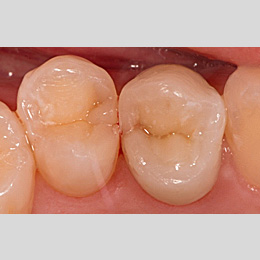

Fallbeispiel: Molarenrevision mit Seitenkanal

Werden im Rahmen einer Wurzelkanalbehandlung nicht alle Bereiche innerhalb des Wurzelkanalsystems ausreichend gereinigt, kann es zu persistierenden Infektionen kommen. In diesem Fall war die persistierende Infektion auf einen feinen Seitenkanal zurückzuführen – mit einer Revisionsbehandlung und gründlicher Reinigung des Wurzelkanalsystems können auch solche persistierenden Infektionen erfolgreich behandelt werden!